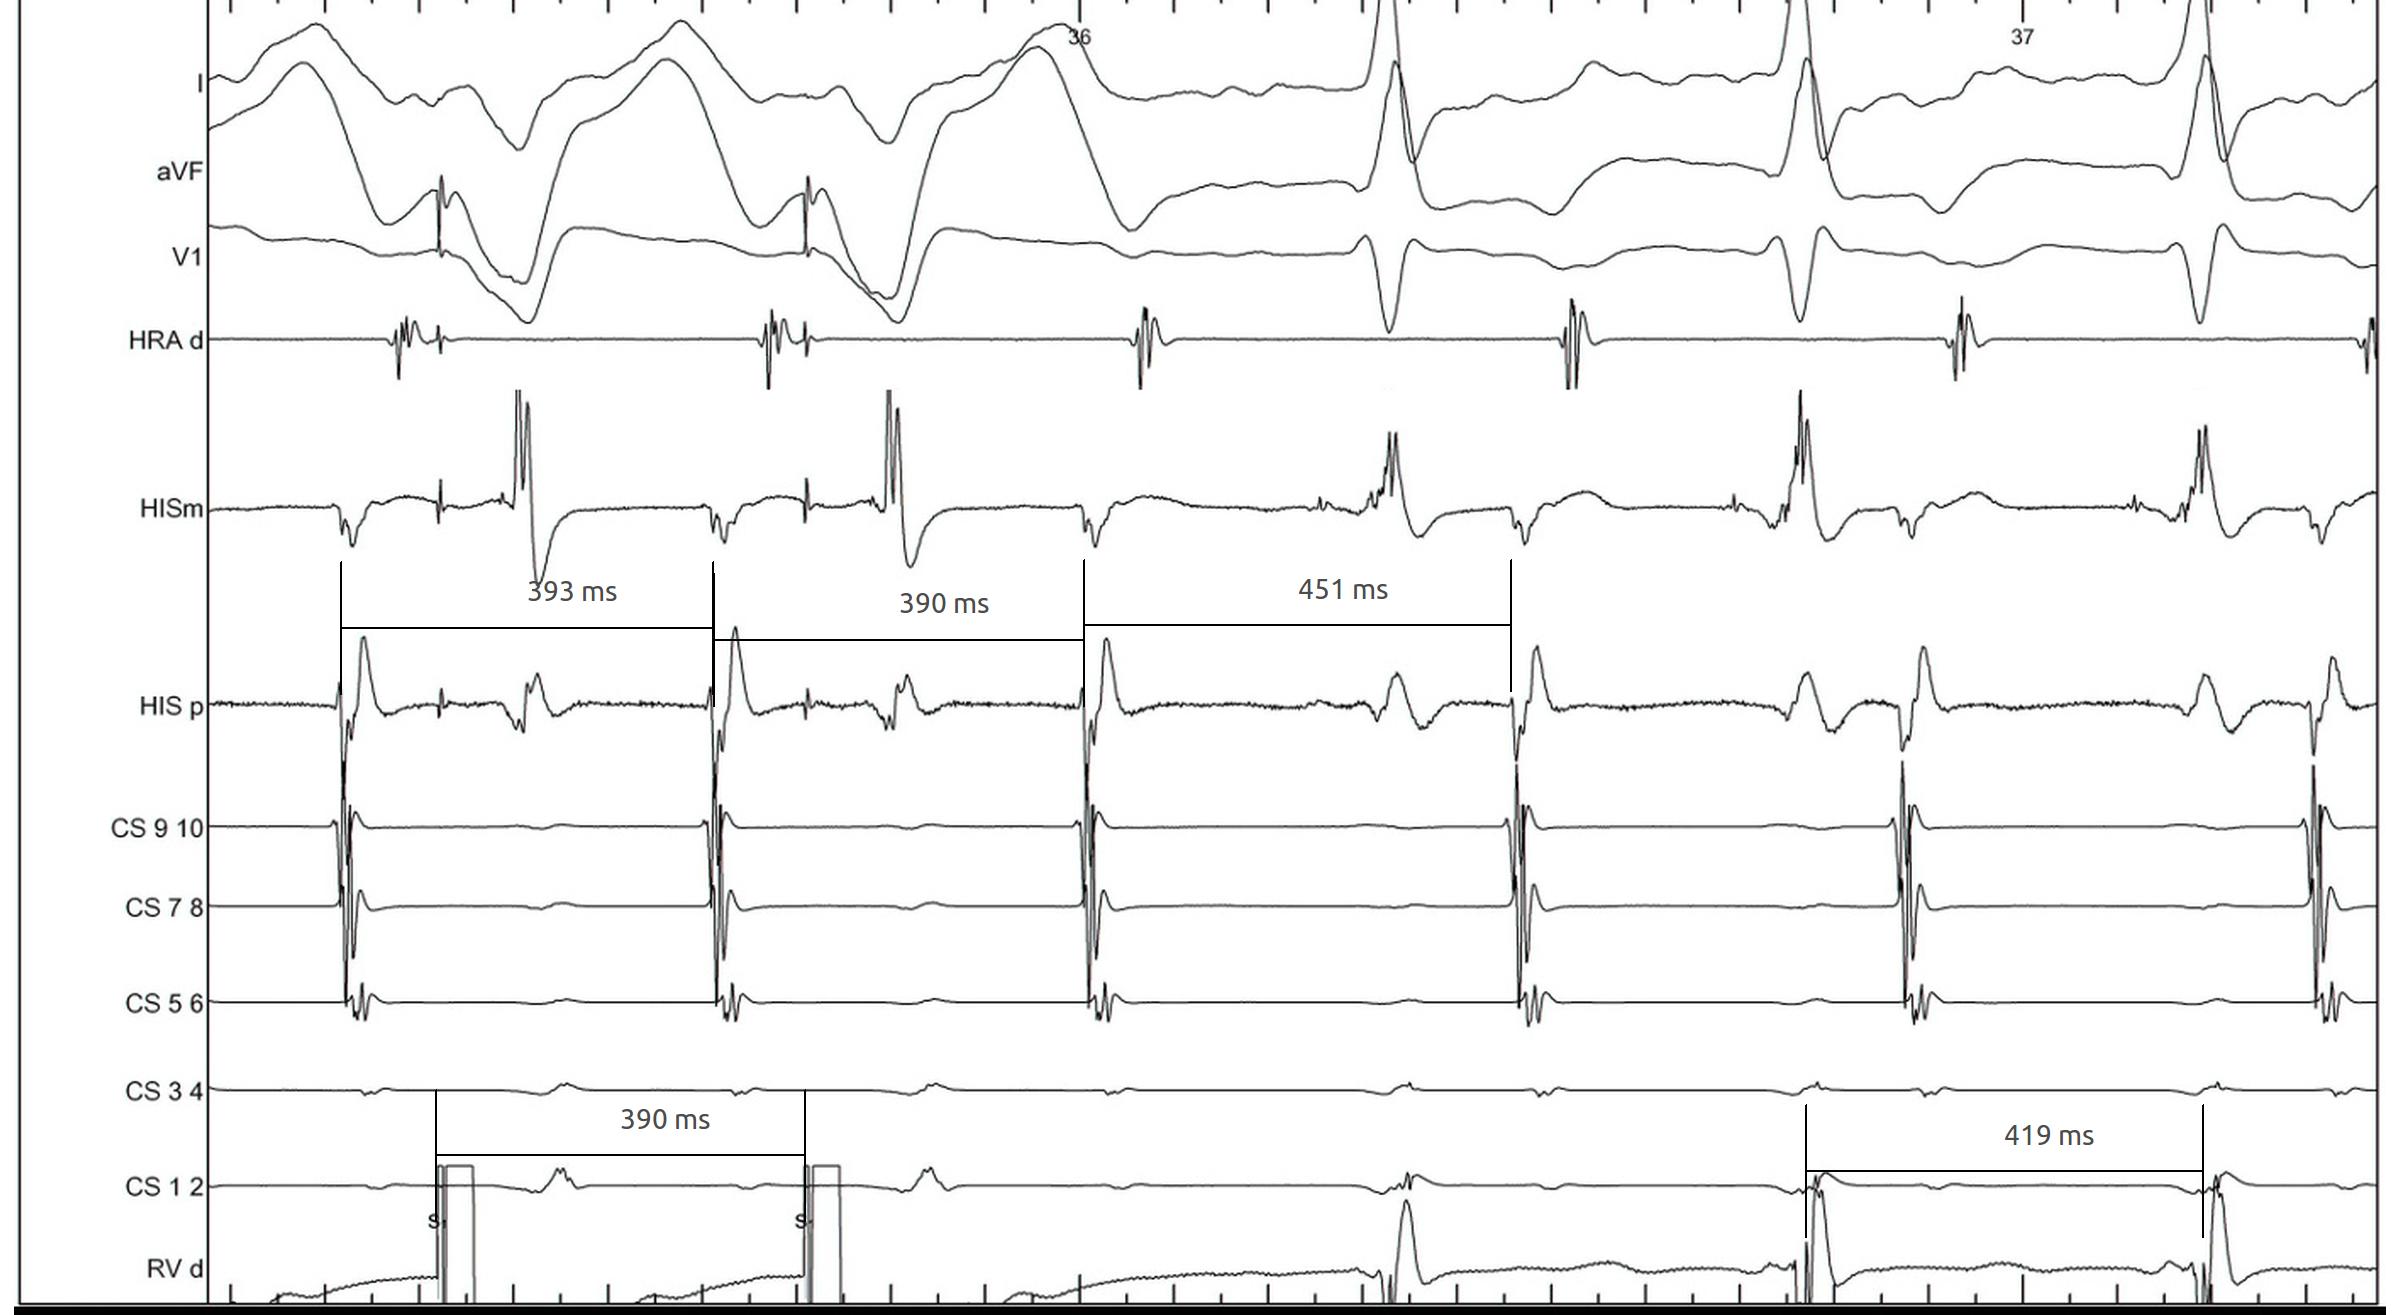

Entrainment

VOP_entrainment.jpg

Beginning of entrainment can give a clue

entrainment_onset.jpg

• Atrial acceleration in transition zone

• A entrainment before H entrainment